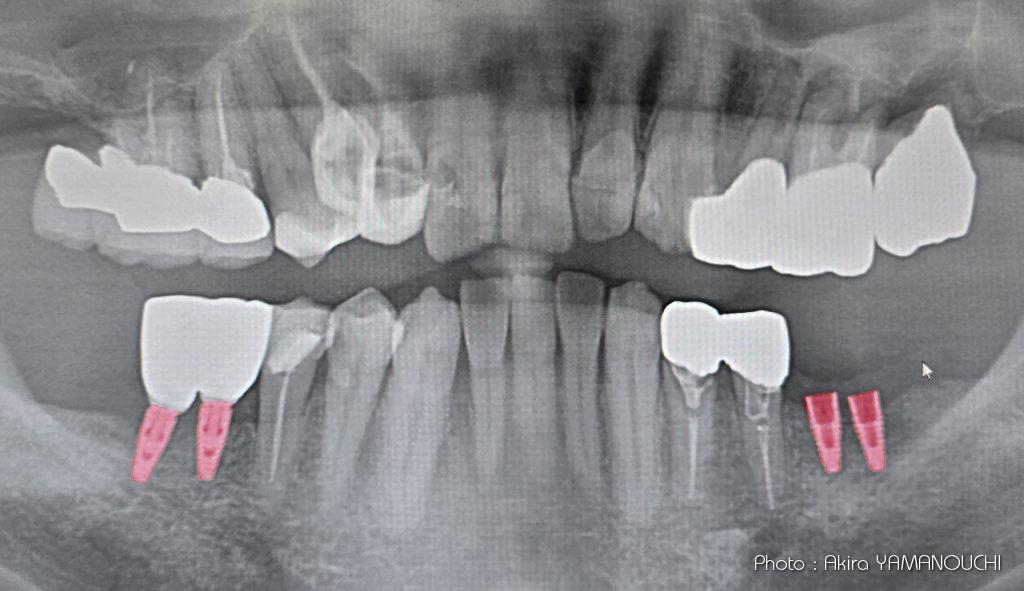

歯がボロボロで公開するのは恥ずかしい。焼死体で発見されたときの歯型照合で役立つかな。

右下インプラントから1年後、左下臼歯2本のインプラントを埋設しました。何か問題が起きて話せなくなったりすると授業ができなくなってしまうので、前期に集中して行う授業が終了してから実行しました。そのため、1年後になりました。